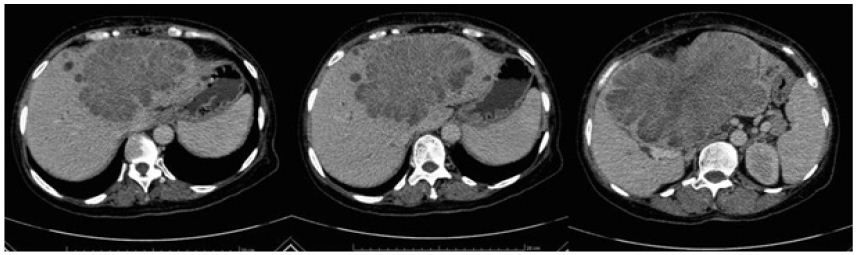

i. The E. neriifolia leaves extract and isolated flavanoid significantly restored the antioxidant enzyme level in the kidney and exhibited significant dose dependent protective effect against DENA induced nephrotoxicity, which can be mainly attributed to the antioxidant property of the extract. This study paid way for the use of hydroethanolic extract of E. neriifolia as anti-carcinogenic potential and for protection of ENF against DENA induced renal cancer [47]. DENA exposed animals showed alterations in normal hepatic histo-architecture, which comprised of necrosis (N), dilated sinusoids and vacuolization of the cells. Mice treated with E. neriifolia lower (ENL) and higher (ENH) dose and ENF before intoxicated with DENA showed that the liver cells were normal, with very little necrosis. The ENH and ENF protect the hepatic tissue against DENA-induced hepatic carcinoma [48].